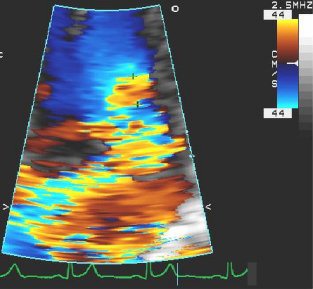

Regurgitação mitral

Corte apical de 4 câmaras de regurgitação mitral 4+ (grave) e uma grande área de superfície de isovelocidade proximal

Do acervo de Samir Kapadia e Mehdi H. Shishehbor